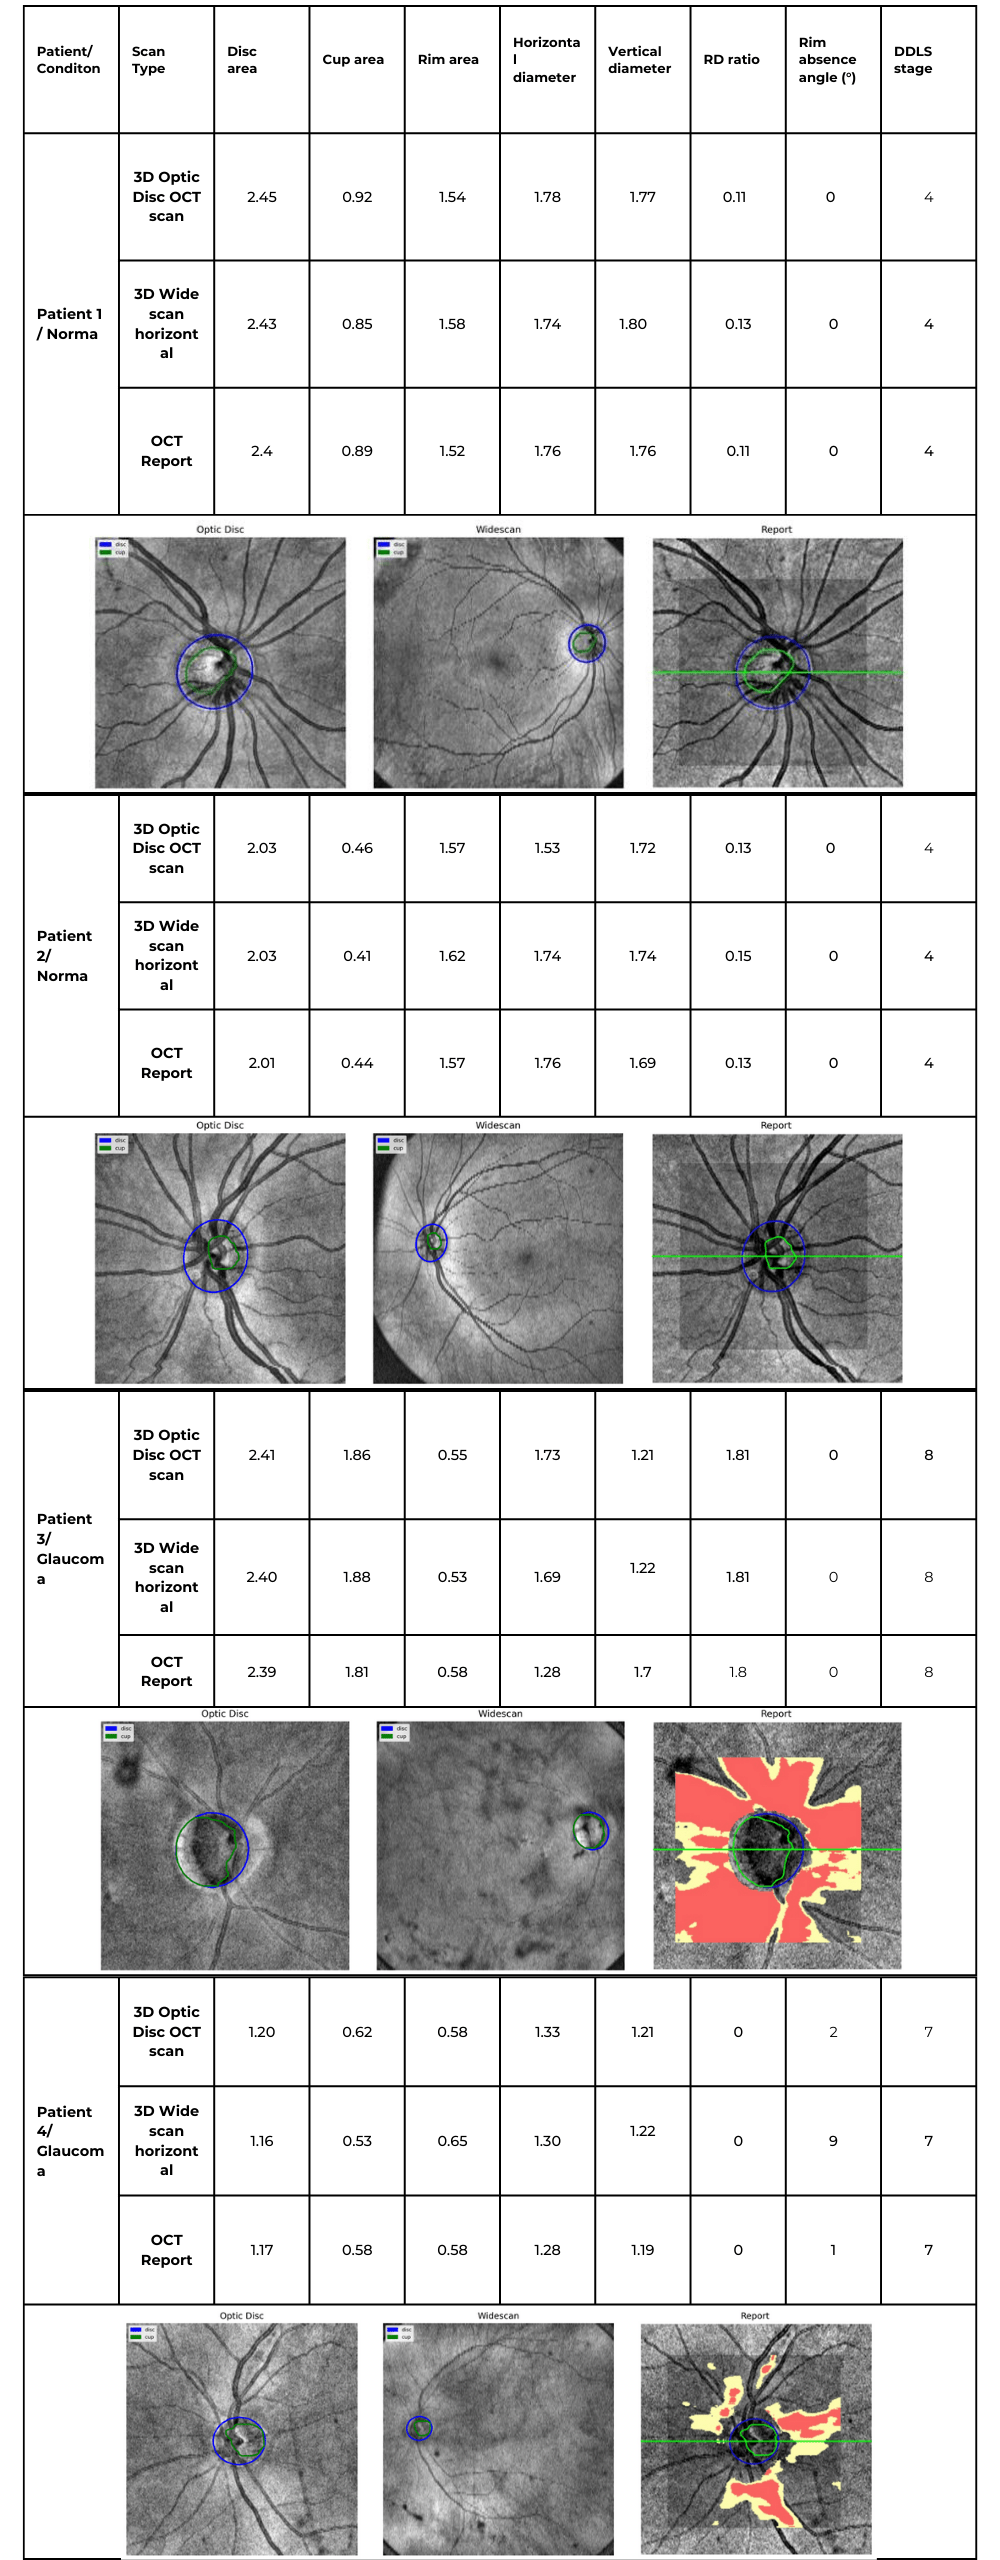

Altris AI’s survey identified a lack of data and increased patient wait times as the top problems with referrals for practitioners, while lack of co-management tools and poor communication/feedback ranked lower.

Let’s dive into more details:

Optometry referral: top problems

Lack of diagnostic data

The ultimate goal of optometry referral is to ensure patients receive appropriate treatment for their specific pathology or confirmation of its absence. The receiving specialist’s first step is to review the referral report, making its completeness and clarity paramount. While there is a clear need for specialised assessment and treatment, almost 80% of those attending eye casualty do not require urgent ophthalmic attention following triage, and up to 60% of patients are seen and discharged on their first visit.

While incorporating images like OCT scans can significantly enhance understanding, some subtle or early-stage pathologies might still be overlooked. This is where detailed and customized reports become invaluable.

To illustrate the point, here is a handwritten referral compared to one of the types of customised OCT report from the Altris AI system, a platform that automates AI-powered OCT scan analysis for 70+ pathologies and biomarkers. This screenshot, in particular, shows segmented retina layers and highlights biomarkers of Dry AMD alongside a comparison of the patient’s macular thickness over visits.